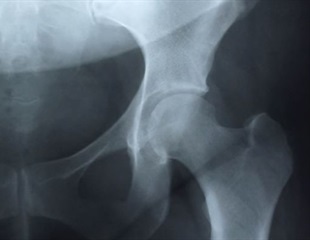

Film X Ray Hip Radiograph Show Stock Photo Edit Now

Babylon, fornitore leader mondiale di soluzioni linguistiche, mette a tua disposizione un traduttore automatico istantaneo per traduzioni di singole parole e frasi da Inglese a Italiano. Il servizio gratuito di Google traduce all'istante parole, frasi e pagine web tra l'italiano e più di 100 altre lingue. Femoroacetabular impingement (FAI) is a condition in which extra bone grows along one or both of the bones that form the hip joint — giving the bones an irregular shape These bones may rub against each other during movement and cause pain.